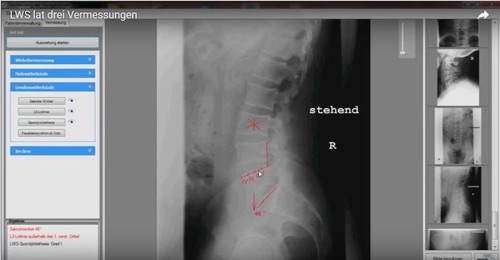

LWS lat drei Vermessungen